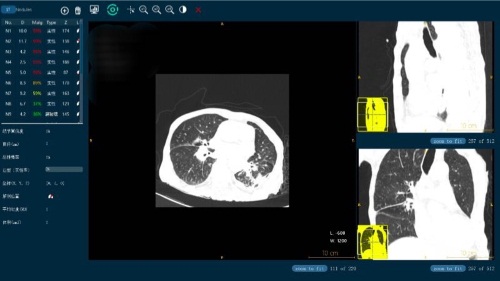

在放射領(lǐng)域,其研發(fā)的肺部CT智能輔助診斷系統(tǒng)Lung-Sight能夠自動檢測病人的結(jié)節(jié)病灶部位并做出定量測算。3-30毫米的結(jié)節(jié)敏感度可達(dá)95%以上,且假陽性控制在2個以下;尤其對于3-5mm的微小結(jié)節(jié)檢測,能大大降低醫(yī)生的閱片時間,同時減少漏診誤診情況。DR-Sight(胸片智能輔助篩查)產(chǎn)品能夠?qū)π男夭课贿M(jìn)行多達(dá)十余種病癥的辨識,可廣泛應(yīng)用于體檢部門和住院門診,協(xié)助醫(yī)生迅速篩檢病癥、標(biāo)識病變位置,并自動生成圖文報告。此項產(chǎn)品已遞交CFDA申請,現(xiàn)已進(jìn)入臨床試驗階段。

微信圖片_20180331092401.jpg

(圖為視見科技的影像產(chǎn)品)